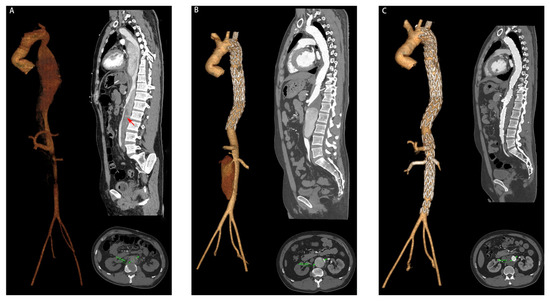

| Partial thrombosis of FL, n (%) | 9 (60.0) | 7 (8.6) | <0.001 |

| Maximum descending aortic diameter (mm), mean ± SD | 41.3 ± 4.5 | 37.5 ± 3.0 | <0.001 |